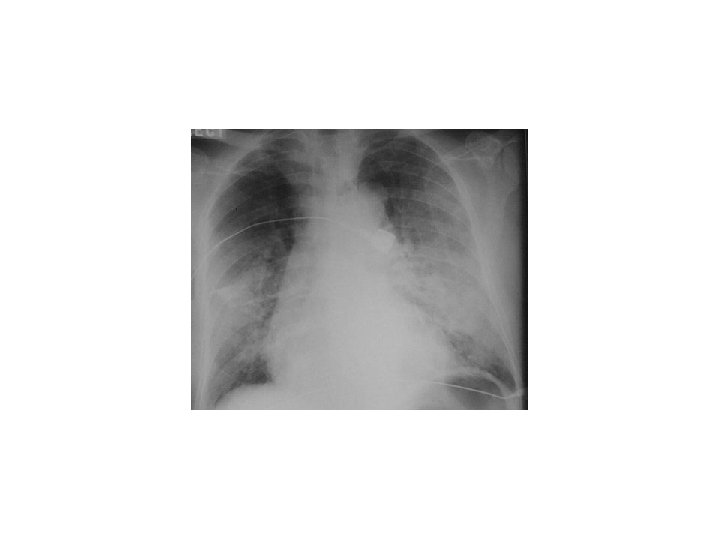

INVESTIGATION § CBC § U+E § LFT § Cardiac enzymes § CXR § ECG § Echocardiogram